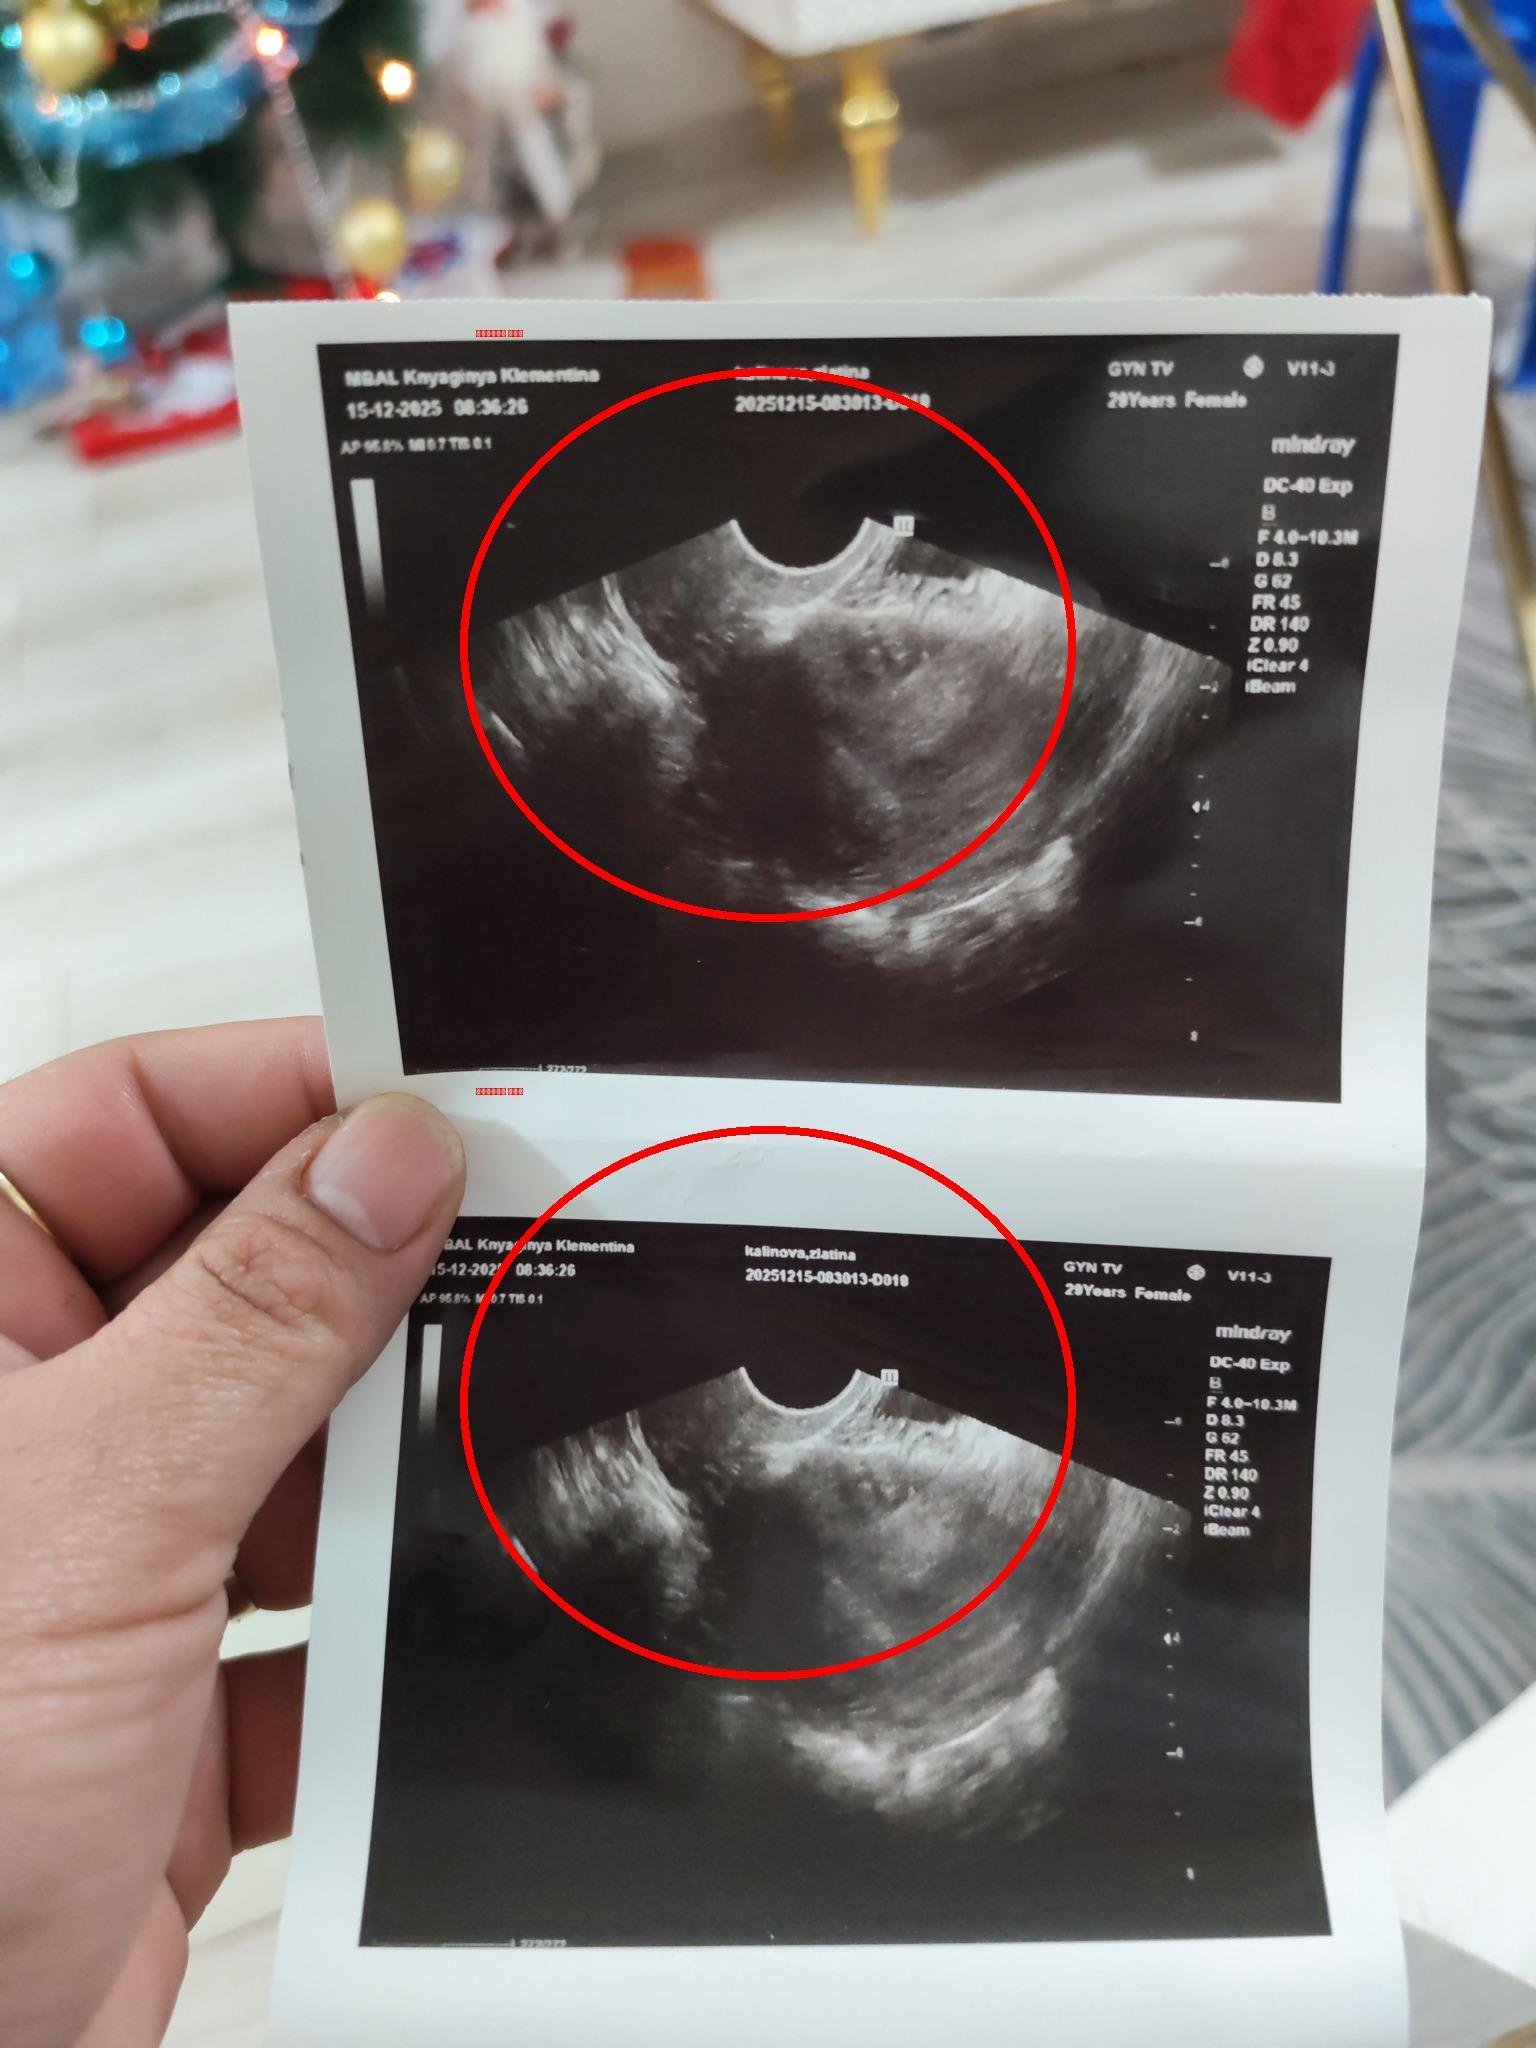

Това са снимки от вчерашният преглед. Не го очетра, като плоден сак, защото било с неправилна форма. Идея си нямате колко лекари ме гледат. И реших да си дам почивка няколко дни, защото психически ще откача

-  в 5+3/5+4 трябва да се вижда вътрематочна бременност. Аз на последните снимки не виждам нищо такова. Така изглеждаше моята двуплоднна бременност в 5+3. Не можеш да го сбъркаш:

- Злати, аз лично болницата, която посещаваш, не я бях чувала дори, като ѝ виждам снимкти и оценката в Гугъл си представям с каква апаратура разполагат. Отиди в Надежда или Токуда, може и Щерев. В Надежда биха те видели и в спешен кабинет като кажеш, че си със съмнения за извънматочна, на другите места предполагам също.

Права е 2402. Нарастването е неправилно и щом има сакче, но с неправилна форма, вероятно се касае за неправилно развитие или мисед.

Неправилната форма често се дължи на липса на ембрионална структура